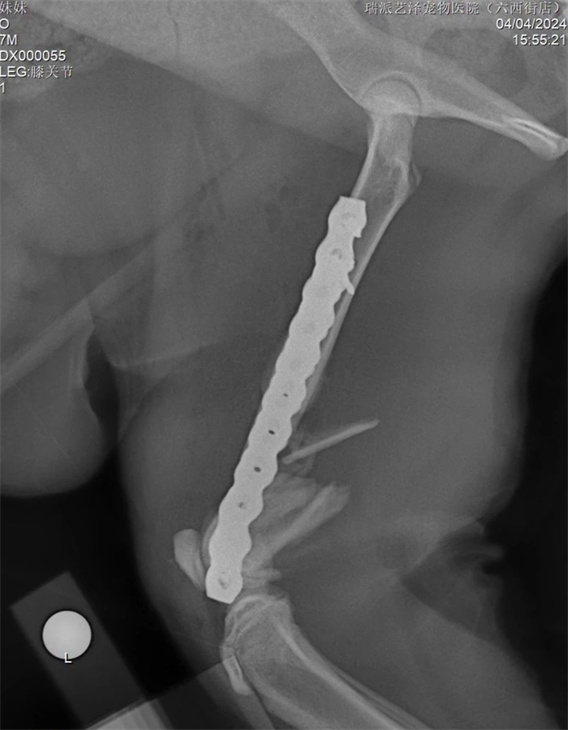

Accidents often occur, leading to various catastrophic consequences. Sometimes we can treat them, but many times we are powerless. This cat jumped from a high place and suffered a severe comminuted fracture. The difficulty of the surgery is; Young cats are considering the issue of femur growth. Fortunately, at the age of 6 months or older, there is not much residual growth space in the distal femur growth plate. Secondly, there is consideration for the animal's inability to effectively restrict movement after surgery, which involves the movement of the distal femur patellofemoral trochlea and knee joint. The fixed structure used should consider factors such as growth, mechanical stability, and bone healing issues. Based on the above considerations, the distal femur is fixed with dual plates on both the inner and outer sides, which are stable and neutralize the axial compressive force of the bone. PRCL-6.5+5mm Bone Plates are used for internal and external fixation. Adopting the lateral pathway of the knee joint and extending to the mid femur. First, perform medial fixation of the femur, which does not require much shaping of the bone plate on the medial side, and then proceed with lateral fixation. Try to use fewer screws when the structure and mechanics are stable, and use locking screws as much as possible for fixation. After surgery, it is necessary to exercise more to avoid muscle adhesion and quadriceps contraction. Preventive 90-90 bandages can be used to fix for 3-5 days.

Follow up and re examination after surgery are all normal.